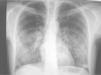

Radiografía de tórax con patrón alveolointersticial en paciente con diabetes mellitus tipo 1 y fiebre